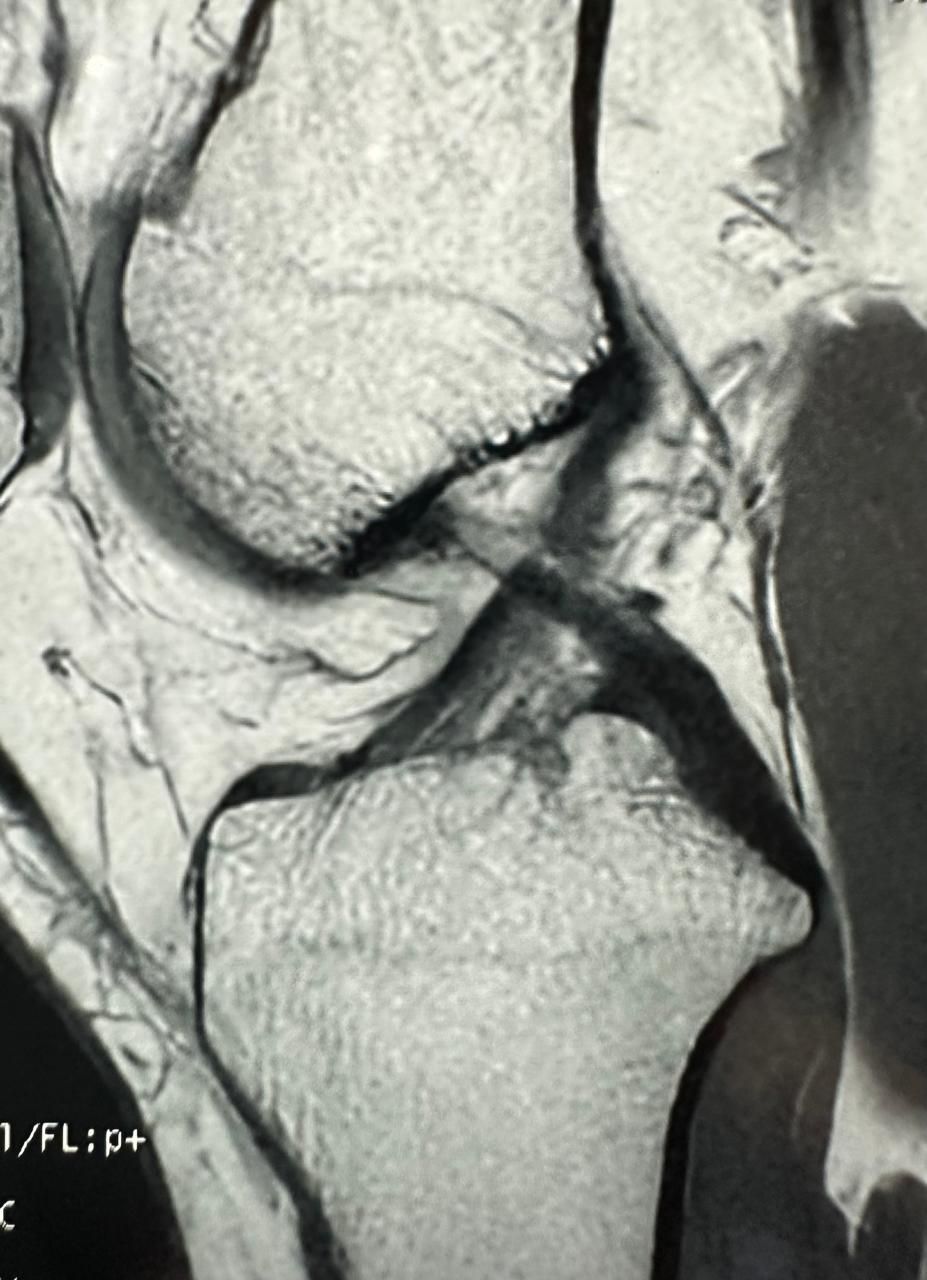

La ortopedia se enfoca en las enfermedades y alteraciones del sistema músculo-esquelético, tanto en adultos como en pacientes jóvenes. El Dr. Juan Carlos Torres Archila, especialista en ortopedia en Comitán, Chiapas, ofrece atención integral y personalizada para afecciones crónicas, degenerativas o congénitas que afectan huesos, articulaciones, músculos, tendones y ligamentos.

Cada caso es valorado a profundidad para proponer tratamientos conservadores (rehabilitación, ejercicios, ortesis) o procedimientos quirúrgicos cuando son necesarios, como artroplastías (colocación de prótesis articulares) o cirugías mínimamente invasivas como la artroscopía.